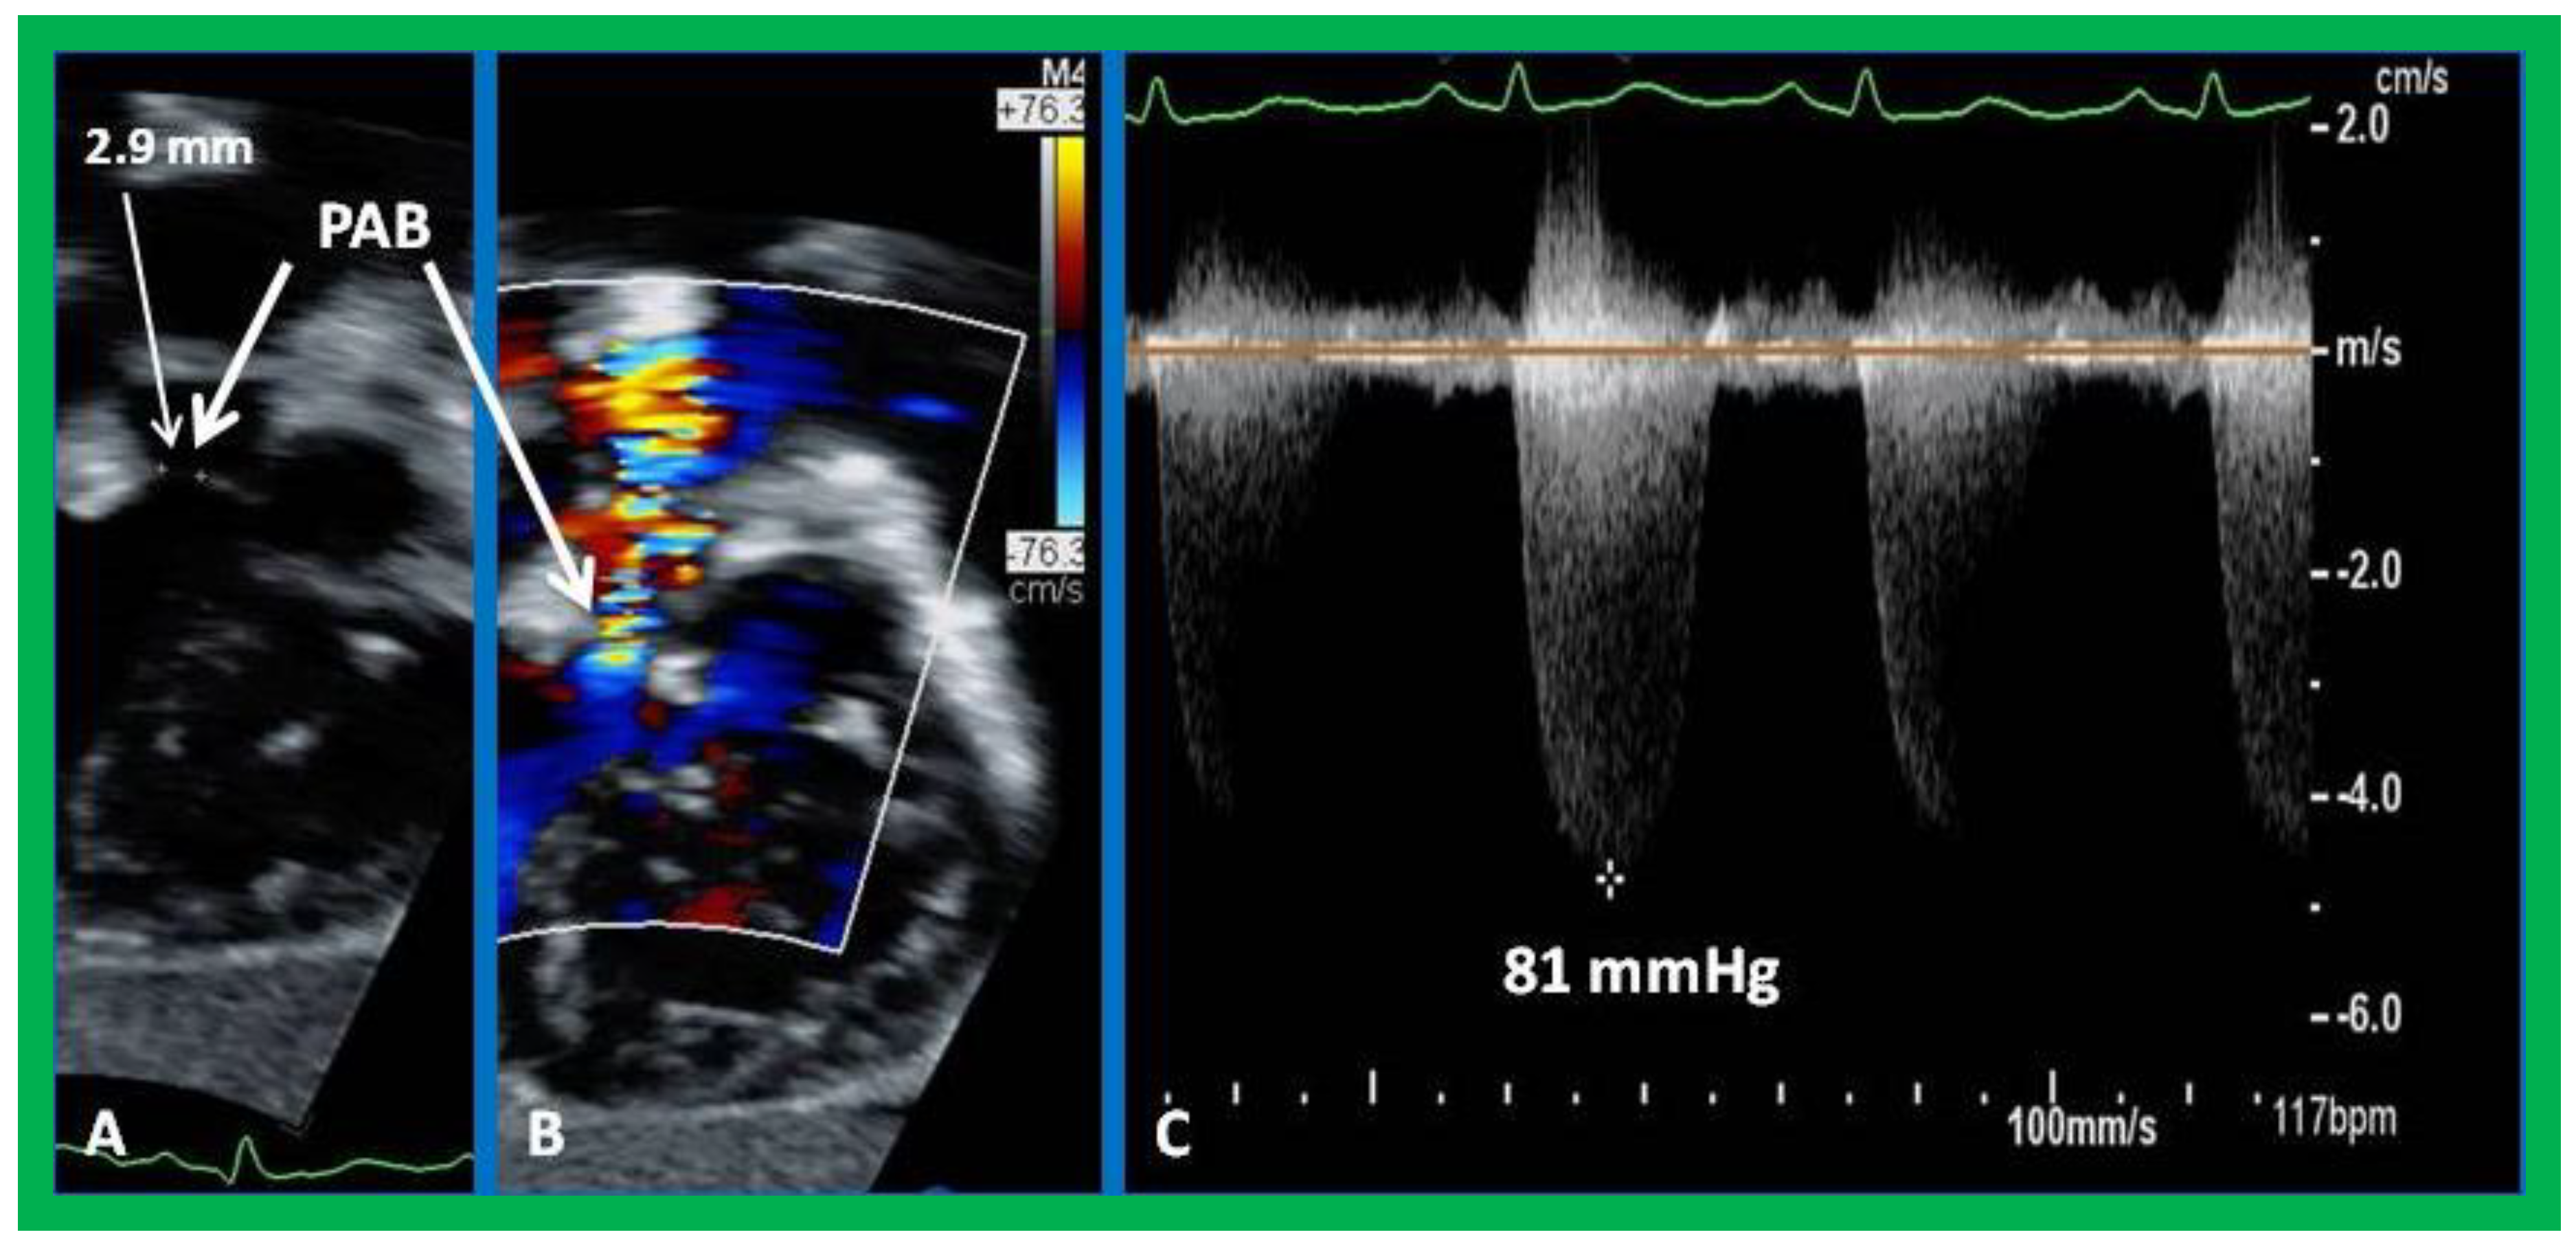

8. Echocardiogram